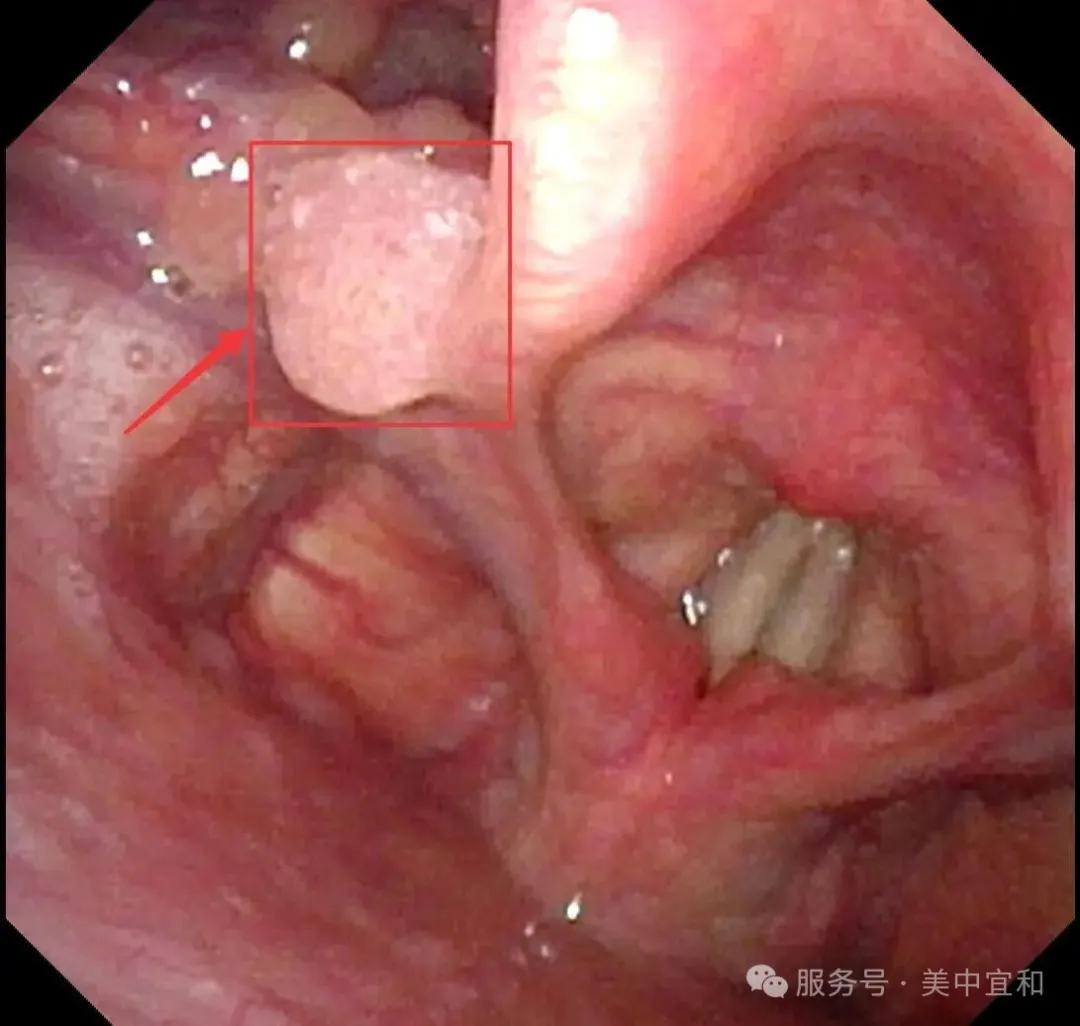

正常會厭部(bu)

會厭左側緣乳頭狀瘤

從(cong)消化內(nei)科(ke)無縫銜接到(dao)耳鼻喉科(ke),由于(yu)疑似腫物(wù)位于(yu)喉腔入口處的(de)會厭部(bu),王主(zhu)任馬上爲(wei)C先(xian)生(sheng)安(an)排(pai)了(le)更爲(wei)精(jīng)細的(de)電(dian)子(zi)鼻咽喉鏡檢(jian)查 ,确診爲(wei)會厭側乳頭狀瘤。

王主(zhu)任提到(dao),這種腫瘤絕大(da)多(duo)數(shu)爲(wei)良性病變,生(sheng)長(zhang)速(su)度相對緩慢,惡變的(de)風險較低,但存在(zai)播散到(dao)其他(tā)黏膜的(de)可(kě)能(néng)。若不及(ji)時治療,腫瘤可(kě)能(néng)累及(ji)并擴散至聲帶等(deng)部(bu)位,可(kě)能(néng)出現(xian)咽喉異物(wù)感,吞咽不适、聲音嘶啞,嚴重(zhong)時腫瘤會阻塞喉腔入口,還可(kě)能(néng)引起呼吸(xi)困難,增加(jia)了(le)治療難度,甚至需要做氣(qi)筦(guan)切開。所幸髮(fa)現(xian)及(ji)時,C先(xian)生(sheng)腫瘤病變還未波(bo)及(ji)到(dao)聲們(men)以(yi)下,王主(zhu)任建(jian)議手術(shù)治療,采用(yong)支撐喉鏡下微創手術(shù),通(tong)過(guo)喉鏡暴露腫瘤後(hou),使用(yong)低溫等(deng)離子(zi)将腫瘤完整切除,這種術(shù)式(shi)創傷小(xiǎo),可(kě)以(yi)最大(da)限(xian)度地保留會厭部(bu)的(de)正常功能(néng),并且有(yǒu)助于(yu)恢複。最終手術(shù)順利完成(cheng),用(yong)時20分(fēn),出血量僅1ml。